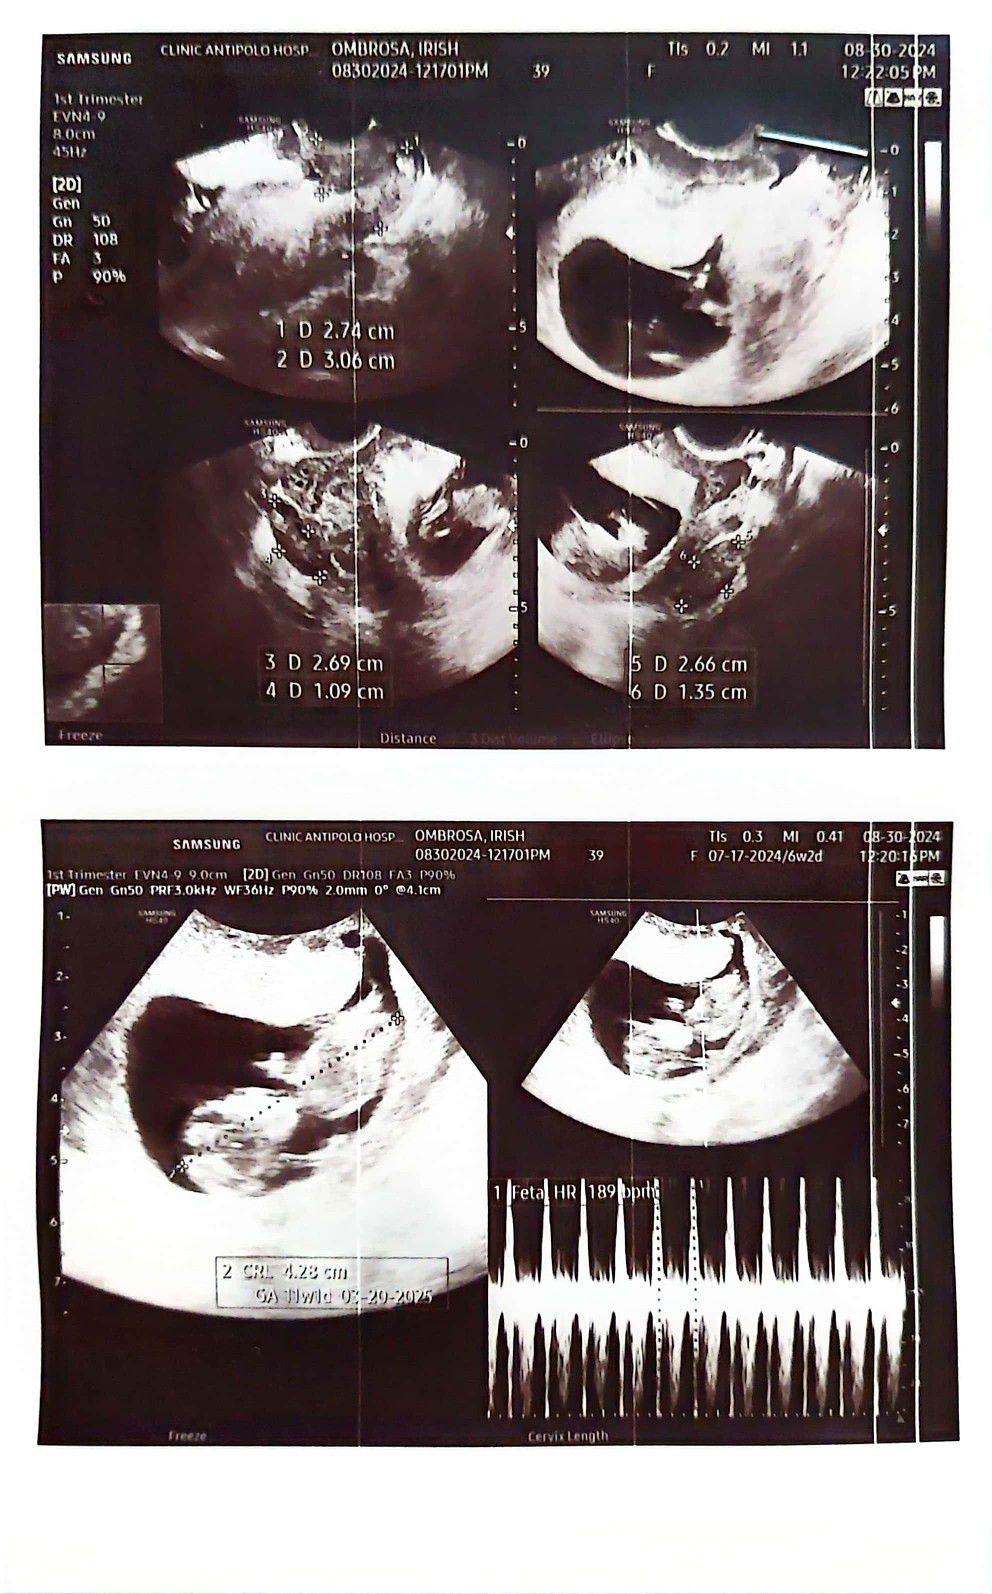

✨️ turns out it's another baby girl 🥰